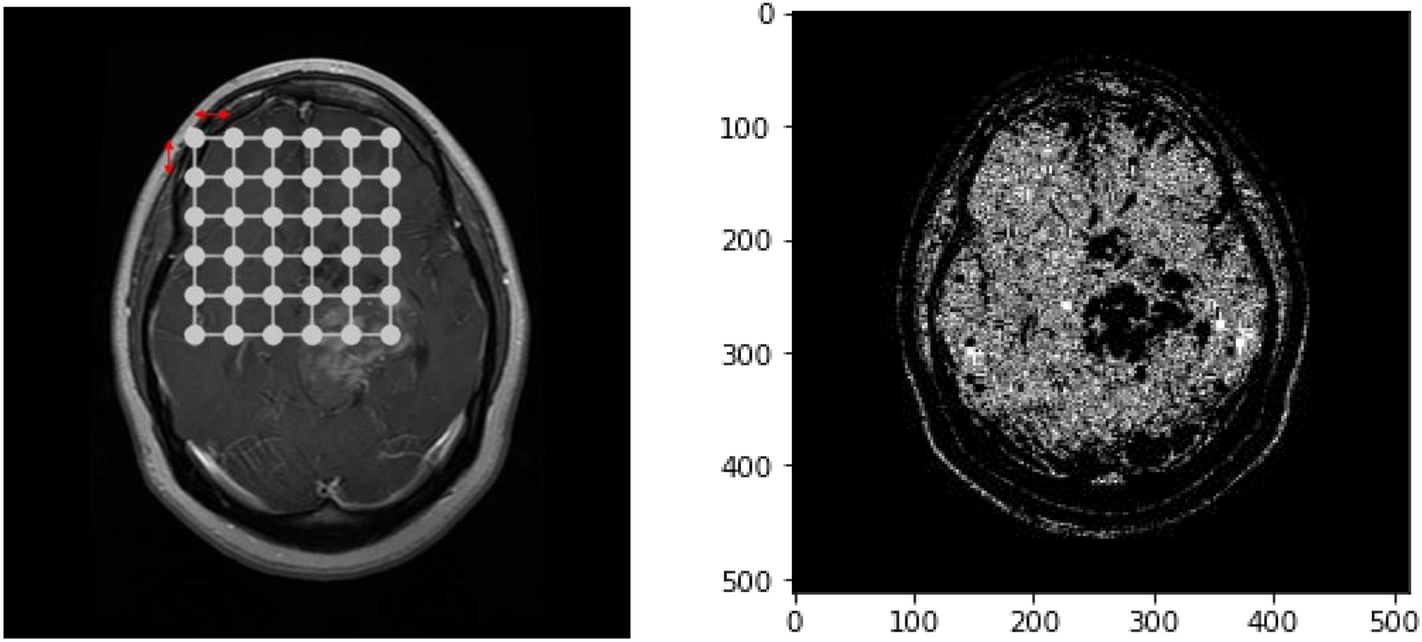

Example output of clustering (left) & Segmentation (right) algorithms without considering Euclidean Distances.